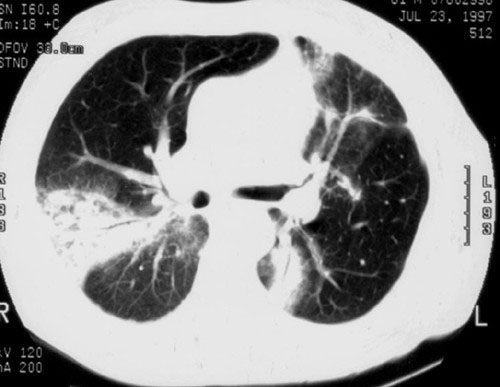

La bronquiolitis constrictiva se caracteriza por una obstrucción significativa del flujo de aire en los bronquiolos, lo cual conduce a una captura de aire que se evidencia en la espirometría. A menudo, los estudios de radiografía de tórax simples pueden mostrar cambios mínimos, mientras que las tomografías computarizadas revelan obstrucción heterogénea del flujo de aire y captura de aire. Clínicamente, los pacientes con bronquiolitis constrictiva experimentan un curso progresivo y deteriorado debido a la severa limitación en el intercambio gaseoso y la función respiratoria comprometida.

Por otro lado, la bronquiolitis proliferativa, anteriormente conocida como neumonía organizadora, se asocia con una variedad de condiciones pulmonares subyacentes como infecciones, aspiración, síndrome de dificultad respiratoria aguda (SDRA), neumonitis por hipersensibilidad, enfermedades del tejido conectivo y trasplante de órganos. En comparación con la bronquiolitis constrictiva, los estudios de imagen como las radiografías simples y las tomografías computarizadas de tórax suelen revelar consolidaciones irregulares, opacidades en vidrio esmerilado o apariencias nodulares periféricas. Funcionalmente, los estudios de función pulmonar típicamente muestran un patrón restrictivo con deterioro de la capacidad ventilatoria y de la oxigenación.

La bronquiolitis respiratoria representa la forma más común de bronquiolitis en adultos, con una fuerte asociación con el tabaquismo. A menudo, esta condición ocurre sin síntomas evidentes ni deterioro fisiológico pulmonar aparente, pero puede estar relacionada con enfermedades pulmonares intersticiales. La TC de tórax en estos casos puede revelar nódulos centrilobulares, opacidades de vidrio esmerilado irregular, captura de aire y opacidades con apariencia de «árbol en brote», características que ayudan en su diagnóstico y manejo clínico.